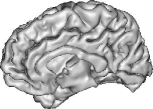

To further investigate the smoothing effect of our reconstruction algorithm, gray matter interface of the cortical surface has bee extracted using the above mentioned BrainVISA pipeline. Extracted surfaces (medial and lateral views) from mSENSE and 3D-UWR-SENSE images are show in Fig. 3 for . For comparison purpose, we provide results with mSENSE at as ground truth.

For the lateral view, one can easily conclude that extracted surfaces are very similar.

However, the medial view shows that mSENSE is not able to correctly segment the brainstem (see right red ellipsoid in

the mSENSE medial view). Moreover, results with mSENSE are more noisy compared to 3D-UWR-SENSE (see left red ellipsoid

in the mSENSE medial view). In contrast, the calcarine sulcus is slightly less accurately extracted with

our approach.

It is also worth noticing that similar results have been obtained on 14 other subjects.